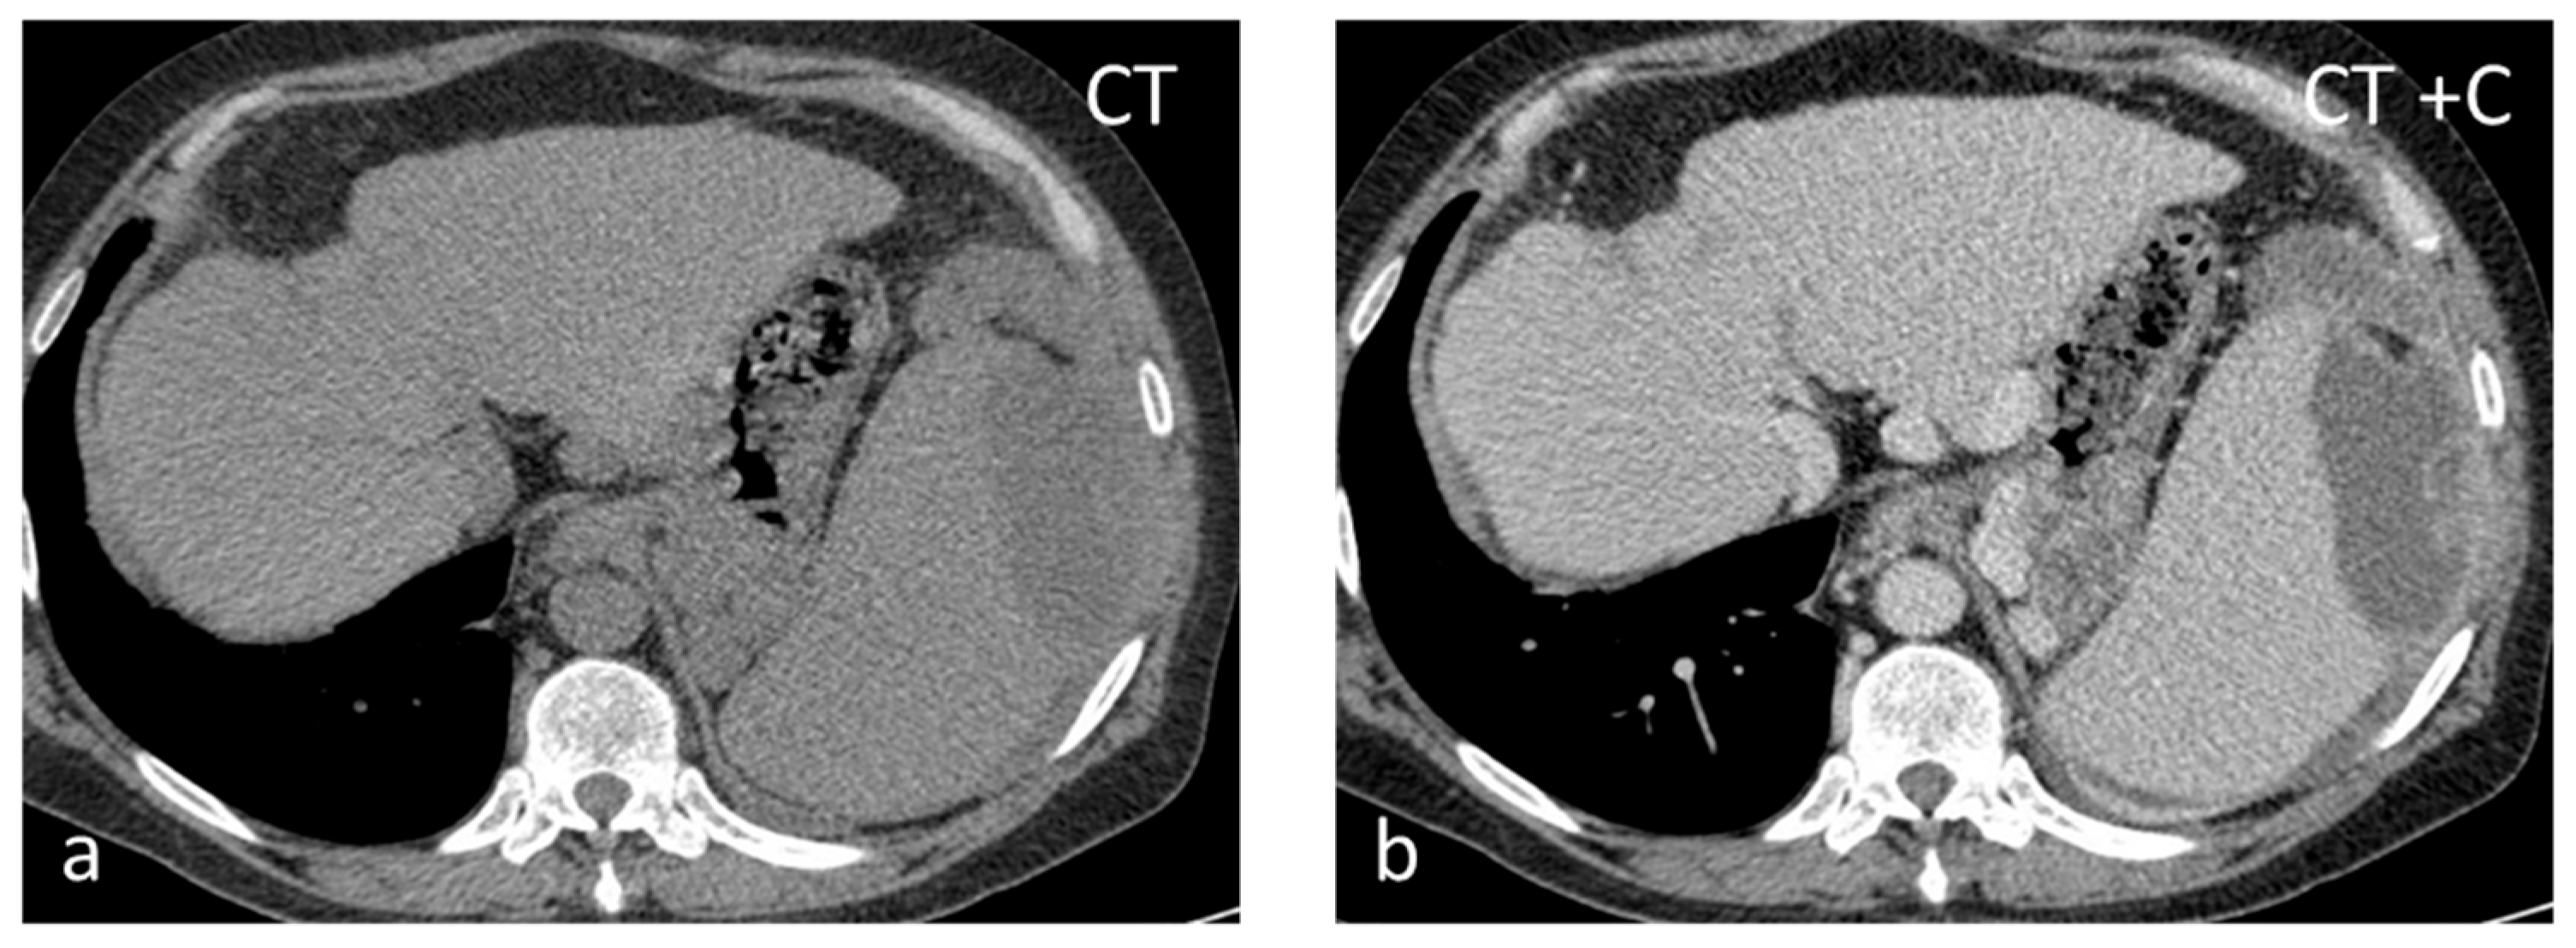

Pyogenic abscesses are rare (incidence between 0.2 and 0.7% in autopsy series) and frequently unrecognized lesions that can be infective (from hematogenous spread or by direct extension), traumatic, post-infarction, or related to immunodeficiency. They can be solitary or multiple. In the majority of abscesses, streptococcus or staphylococcus is isolated. In the presence of a pyogenic splenic abscess without obvious etiology, it may be helpful to investigate bacterial endocarditis as a possible source of septic emboli [44]. On US, pyogenic abscesses appear as ill-defined hypoechoic or anechoic lesions with debris, fluid levels, and internal septations of varying thickness. Intralesional gas causing echogenic foci with ‘dirty’ shadowing is highly suggestive [45]. CT shows ill-defined lesions with inhomogeneous low attenuation (Figure 8). At MRI, they present with fluid lesion characteristics and show peripheral irregular rim enhancement [46].

Figure 8.

Thirty-seven-year-old male with HIV-HCV infection and splenic abscess from E. coli. The abscess appears as an ill-defined, subcapsular lesion with hypodense content on non-contrast CT (a) and thick irregular enhancing wall post intravenous contrast administration (b).